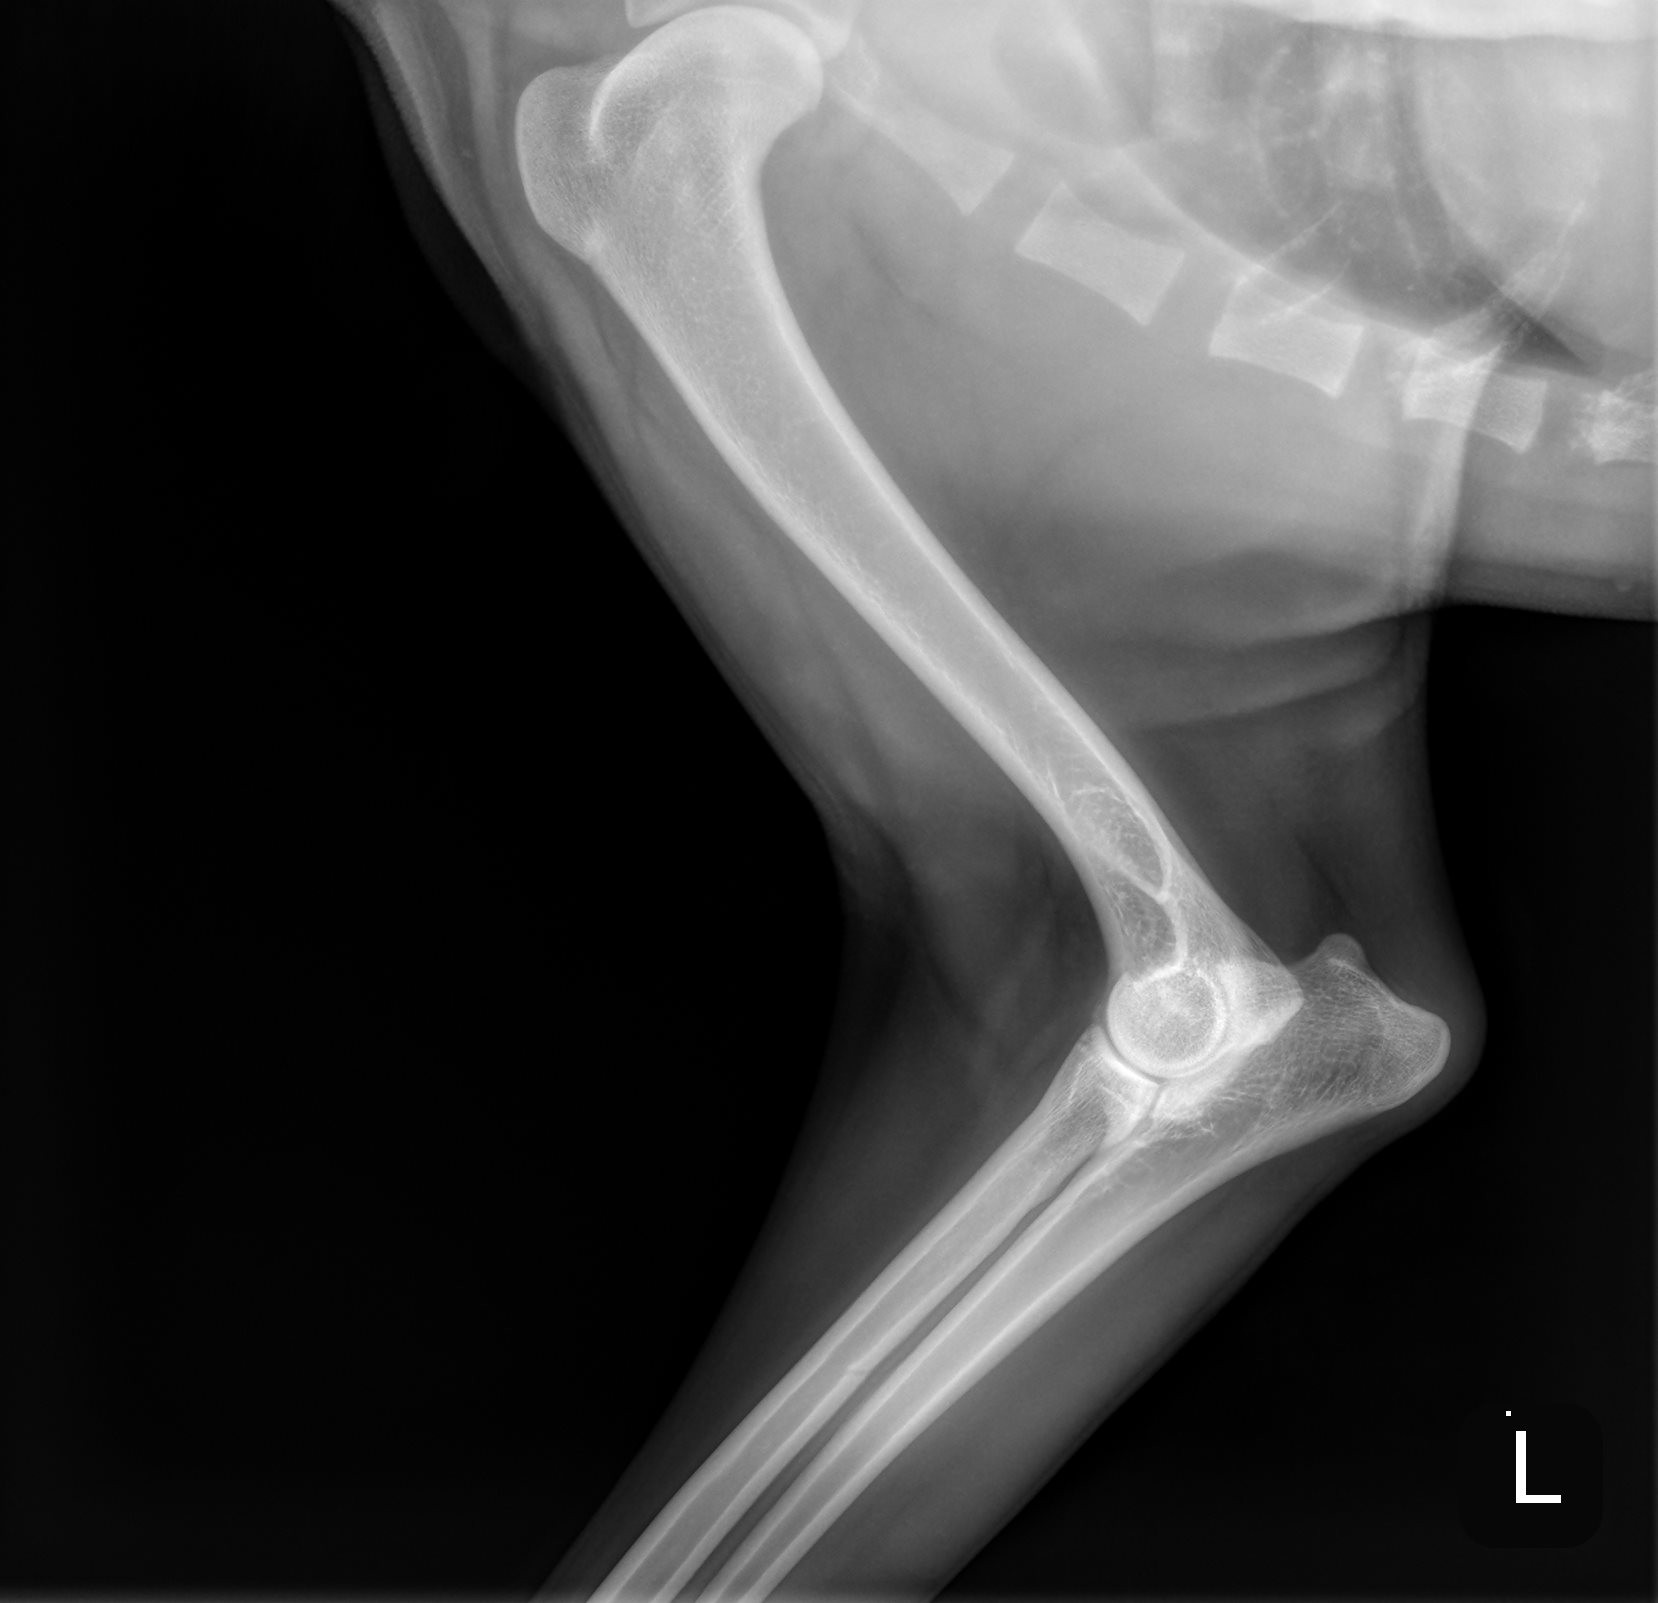

River is a sweet, gentle 1 1/2 year old golden, who had a tragic fall down a flight of stairs and fractured his humerus bone. Due to financial hardship and the physical challenges of navigating multiple flights of stairs, River’s family made the heartbreaking decision to surrender him to GRR so he could receive the care he desperately needed.

This type of injury is incredibly painful and requires specialized surgery to repair. Without it, River’s chances of ever walking, playing, or living a pain-free life are at risk. Watching him struggle to stand and looking into his eyes as he winces in pain is heartbreaking.

On Tuesday (10/30/2025) afternoon, his leg was surgically repaired using plates, screws & pins.  We are hoping his will be fully recovered in 8 weeks.